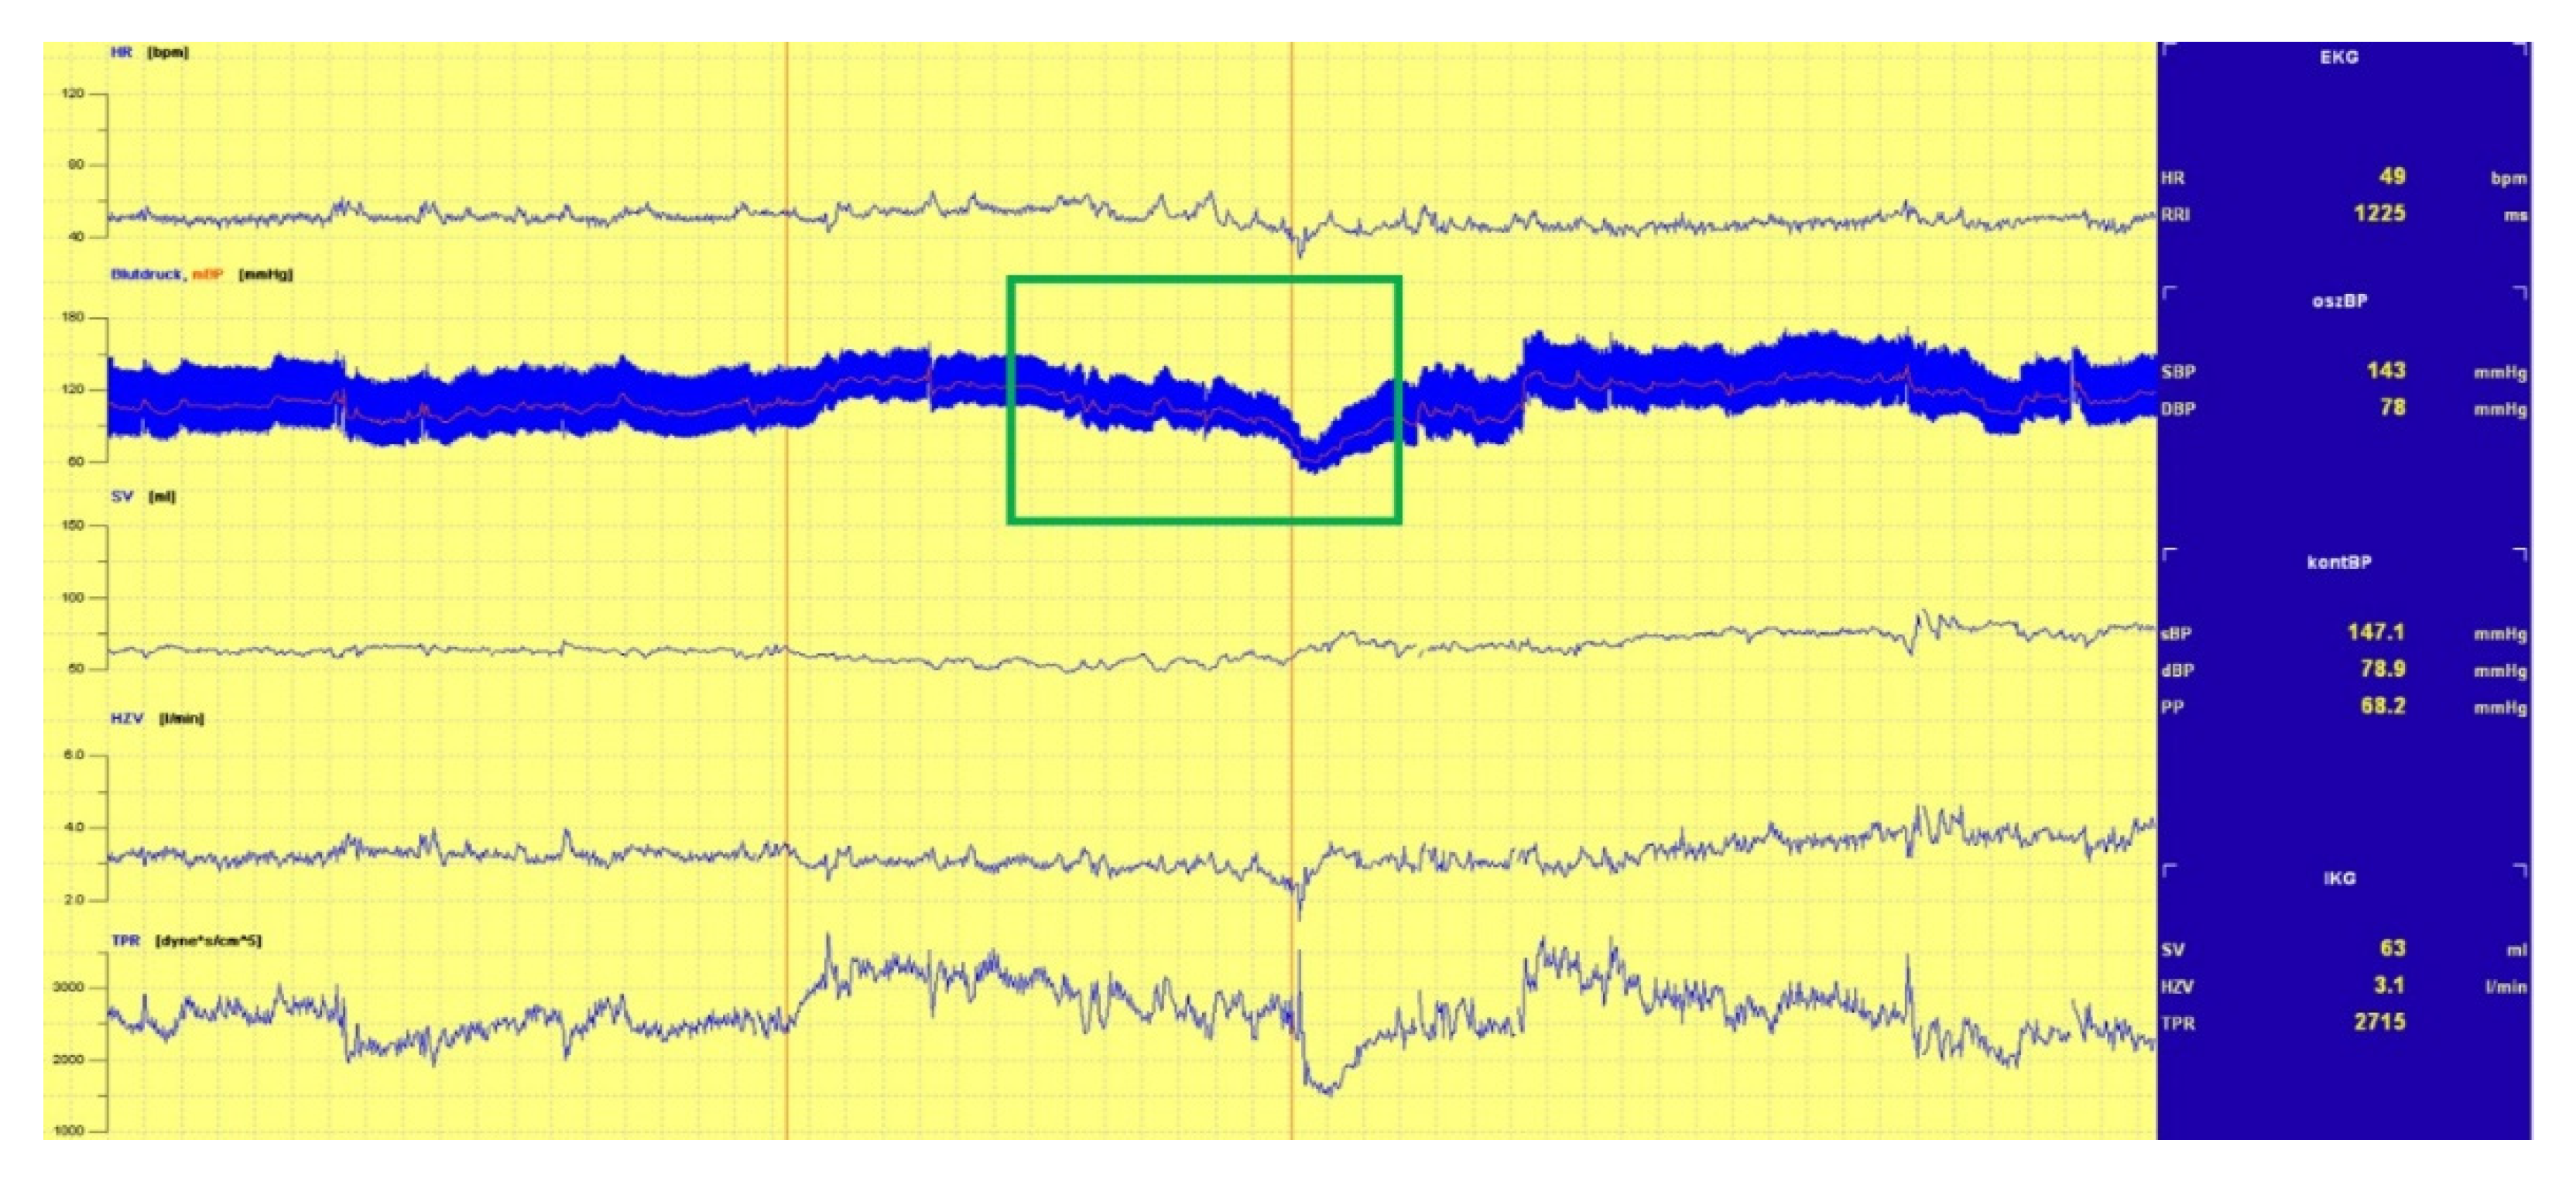

3.1.1. Head-Up Tilt (HUT) Test